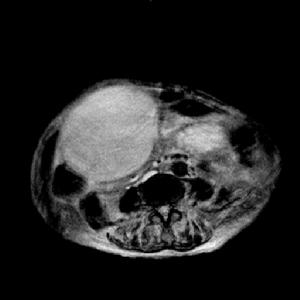

巨大肝囊腫出血(1)巨大肝囊腫:少數肝囊腫生長速度較快,當囊腫直徑超過10厘米,稱之為巨大肝囊腫。近年來,有採用超聲引導下進行囊腫穿刺抽液,囊腔內注入適量無水酒精,可使囊腔閉合;單發性巨大囊腫也可考慮切除;多發性囊腫可考慮部分肝切除術。

巨大非寄生蟲性肝囊腫2.單發性囊腫直徑5~10cm者或多發性肝囊腫,有2個直徑>5cm者,可考慮手術治療。有腹部包塊、疼痛或壓迫症狀明顯,或有併發症時,應考慮手術治療。

對於孤立性肝囊腫除非發生囊腫破裂囊蒂扭轉,或囊內出血等併發症進行緊急手術治療外,擇期手術需要根據囊腫的大小部位病人的全身情況,自覺症狀而定。體檢中偶爾發的無症狀的孤立性肝囊腫,可暫時採用保守治療,利用超聲檢查,定期觀察需要警惕惡變的發生大的肝囊腫,有症狀出者最好施行手術治療,因為穿刺抽液等保守療法一般容易復發,並且帶來細菌污染。可多囊肝通常應採取非手術治療。由於其病變累及整肝臟,除非採用肝移植,否則不根治本病然而多囊肝,一旦由於肝腫大壓迫胸腹部,影響呼吸循環時需考慮手術,減輕壓力可根據具體條件用下手術方法: